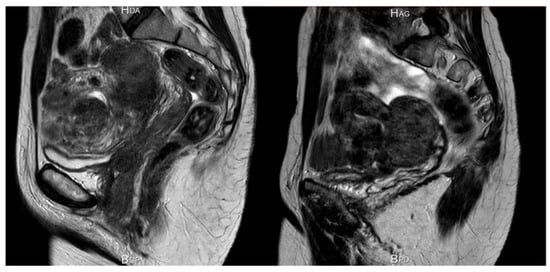

3.3. Increased Uterine Contractility

One study using MRI demonstrated that intramural myomas induced abnormal uterine peristalsis, resulting in lower implantation and pregnancy rates [34]. The same team reported that myomectomy decreases abnormal uterine peristalsis and increases pregnancy rates [35]. According to Fanchin et al. [36], uterine contractility diminishes in response to progesterone to favor embryo implantation. If the presence of intramural myomas alters uterine peristalsis, it may also affect the surrounding myometrium and lead to impaired uterine contractility.